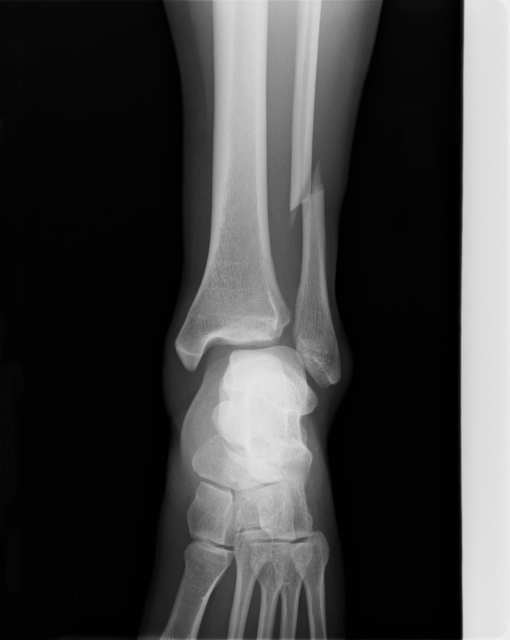

• 診断・治療方針:画像診断・手術適応判定

• 荷重許可:段階的荷重増加の医学的判断